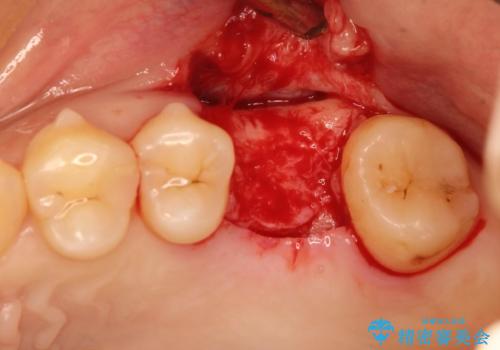

- 歯根破折を生じた奥歯を抜歯後、治癒の期間を経てインプラントを埋入

→2時手術の後、インプラントレベルの型どりにて上部構造まで完成させる